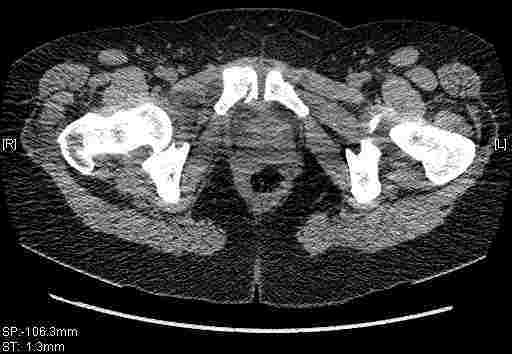

Удалось сегодня вывести пациентку в соседнюю больницу, где есть кт. Срезы сделаны только горизонтальные.

Следом 3d